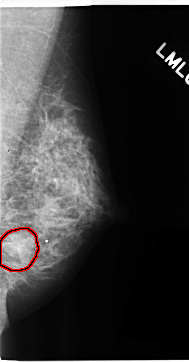

C_0153_1.LEFT_CC

LEFT_CC LINES 4712 PIXELS_PER_LINE 2648 BITS_PER_PIXEL 12 RESOLUTION 50 OVERLAY

FILE: C_0153_1.LEFT_CC.OVERLAY

TOTAL_ABNORMALITIES 1

ABNORMALITY 1

LESION_TYPE MASS SHAPE LOBULATED MARGINS ILL_DEFINED

ASSESSMENT 4

SUBTLETY 1

PATHOLOGY MALIGNANT

TOTAL_OUTLINES 1

BOUNDARY